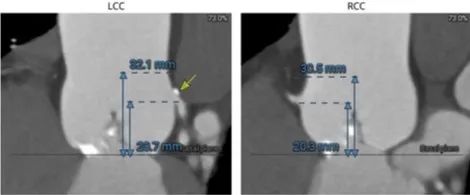

主动脉瓣根部:

主动脉瓣根部,Type 1二叶瓣有钙化嵴: